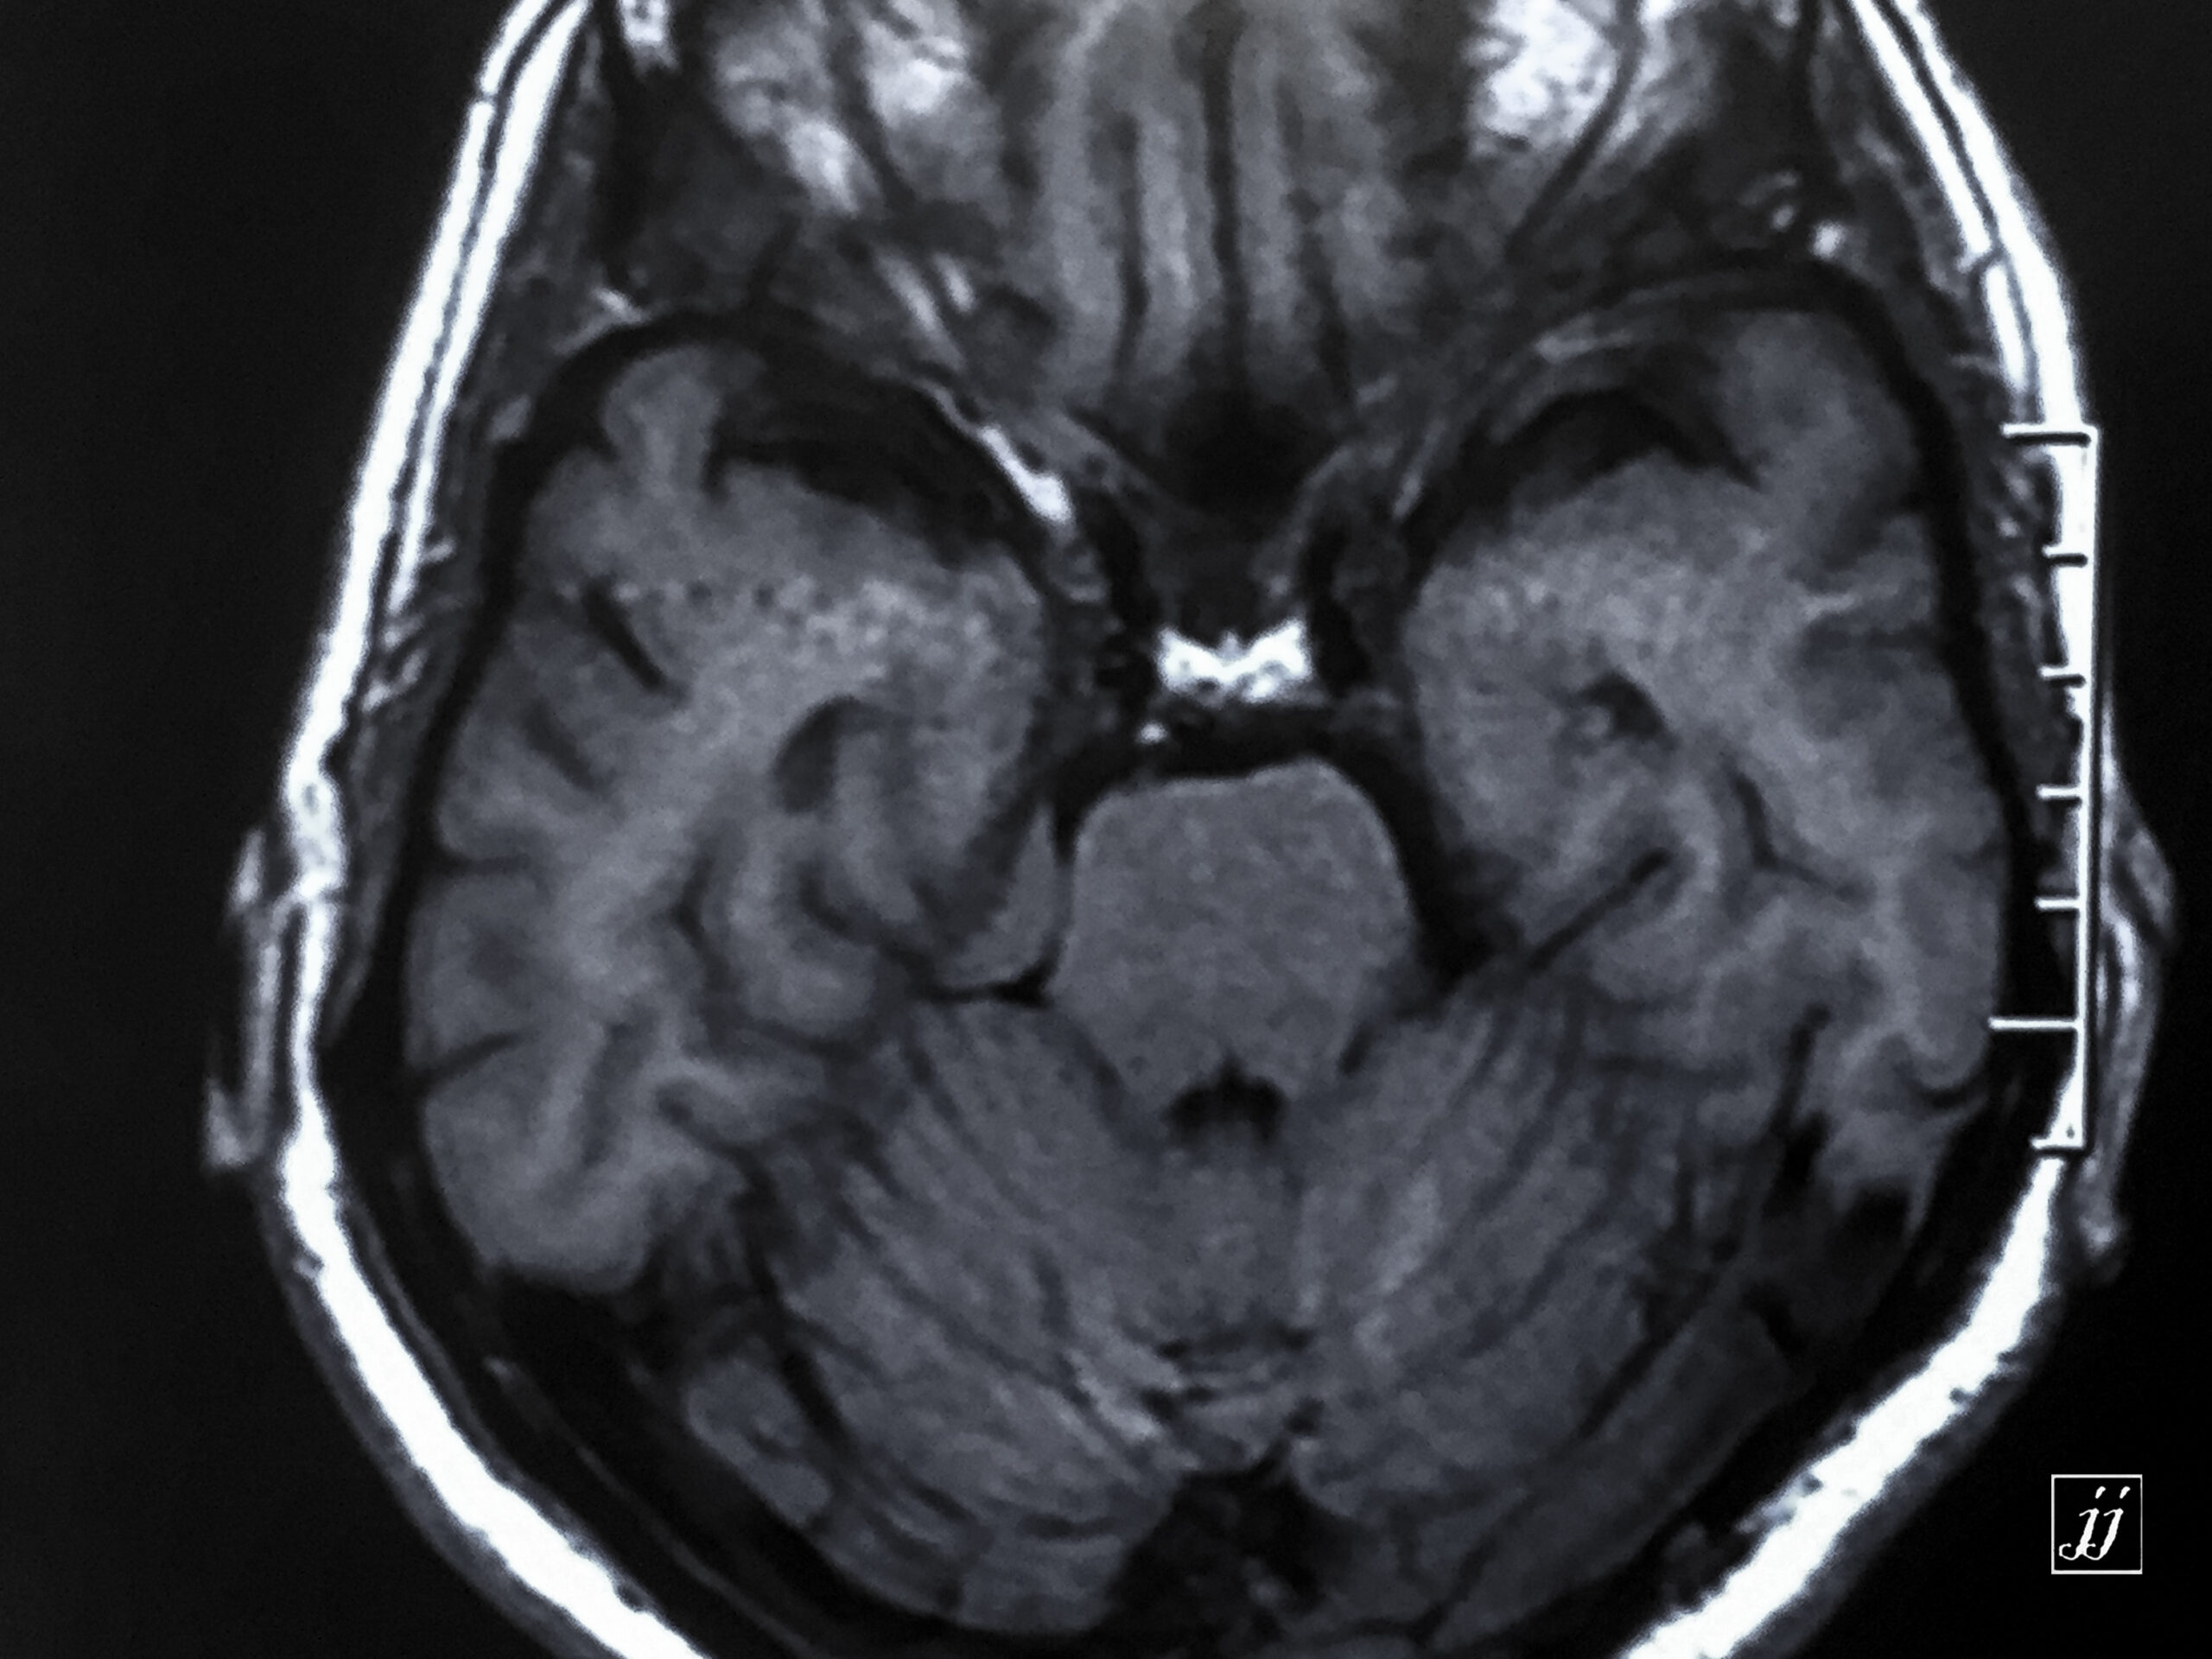

Brain- small right CPA Meningioma (5)